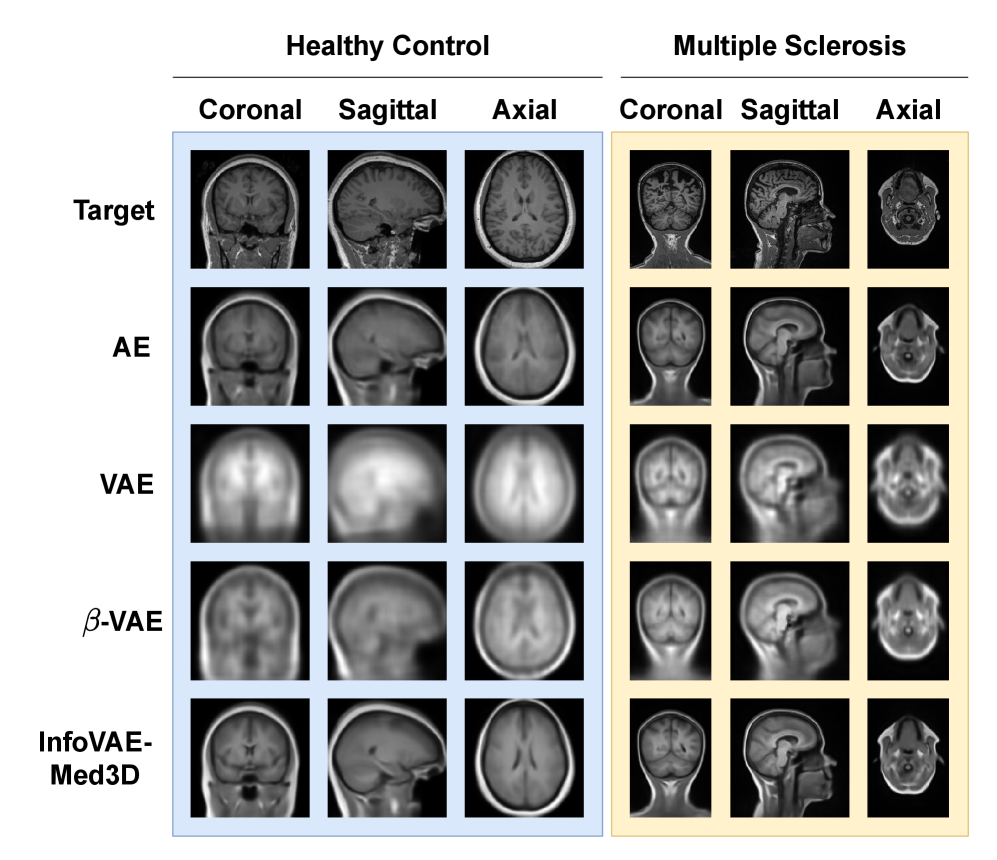

Figure 1 shows reconstructed images along three anatomical planes, comparing InfoVAE-Med3D against three VAE variants for the two datasets: HC (blue, left side) and MS (yellow, right side). In general, image blurriness is a common limitation of the VAE family, but our model achieves clearer reconstructions, although still not highly detailed. Standard VAE (row 3) and β\beta-VAE (row 4) produce relatively coarse results, capturing only the outer brain shape with very limited internal details such as the cerebellum or cortical regions. In contrast, AE (row 2) yields sharper reconstructions, and InfoVAE-Med3D (bottom row) further improves both structure and clarity. Our model shows cortical volume and skull boundaries more clearly, as well as the separation between hemispheres in the coronal view. Furthermore, features such as the ears, and parts of the nose and mouth are better reconstructed in the sagittal view, and the cerebellum and eye sockets are more clearly preserved in the axial view. These qualitative improvements suggest that InfoVAE-Med3D preserves more anatomically meaningful details for downstream analysis.

Figure 1: Qualitative comparison of InfoVAE-Med3D with three VAE variants across coronal, sagittal, and axial views. Two examples are shown: a BrainAge sample (left, blue background) and a Prague sample (right, yellow background).